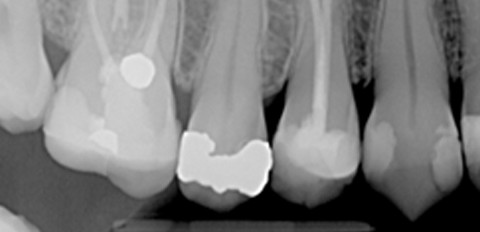

Abb. 1: Röntgenaufnahme mit einer Speicherfolie. Abb. 2: Röntgenaufnahmen mit einem Festkörpersensor.

Intraorale Festkörper-Sensoren lassen sich am Patienten schwerer positionieren und sind im Gebrauch unhandlicher als Speicherfolien. Letztere können mit konventionellen Haltersystemen exponiert werden und haben bezüglich ihrer mechanischen Festigkeit große Ähnlichkeit zum konventionellen Film. Sie lassen sich deutlich besser anatomischen Gegebenheiten anpassen und ihre einfache Handhabung erleichtert den Umstieg von der konventionellen zur digitalen Technik. Die Anzahl der Lesezyklen wird mit mehreren Hundert bis mehreren Tausend sehr unterschiedlich angegeben. Sehr schnell fällt jedoch die empfindliche Oberfläche der Speicherfolien auf, welche durch das Einbringen in Haltersysteme oder auch durch zu spitze Fingernägel häufig in Mitleidenschaft gezogen wird. Die Bildqualität von Speicherfolien (Abb.1) ist der von Festkörpersensoren (Abb. 2) mindestens vergleichbar, als Beispiele können hier die Systeme VistaScan (Dürr Dental, Bietigheim-Bissingen) und DIGORA®Optime (Soredex Deutschland, Schutterwald) genannt werden.